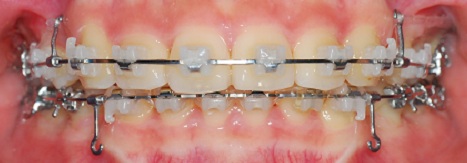

치아 정면사진이에요

발치공간 정말 많이 줄엇죠?

의사선생님이 이동이 빠르다구 하셨어요

사진을 보면 위에 왼쪽은 스크류가 있고 스크류에 고무줄을 걸었구요

오른쪽은 스크류를 빼고 치아에 있는 장치로만 고무줄을 걸어놨어요.

아래는 위와 이동하는 속도를 맞추기 위해 고무줄을 걸지 않았습니다.

왼쪽은 위아래 속도를 맞춰서 잘 가는데

오른쪽은 속도가 조금 안맞는다구 하셨어요

그리구 아래 앞니들에 고무줄 걸구 이번치료는 끝*^^*